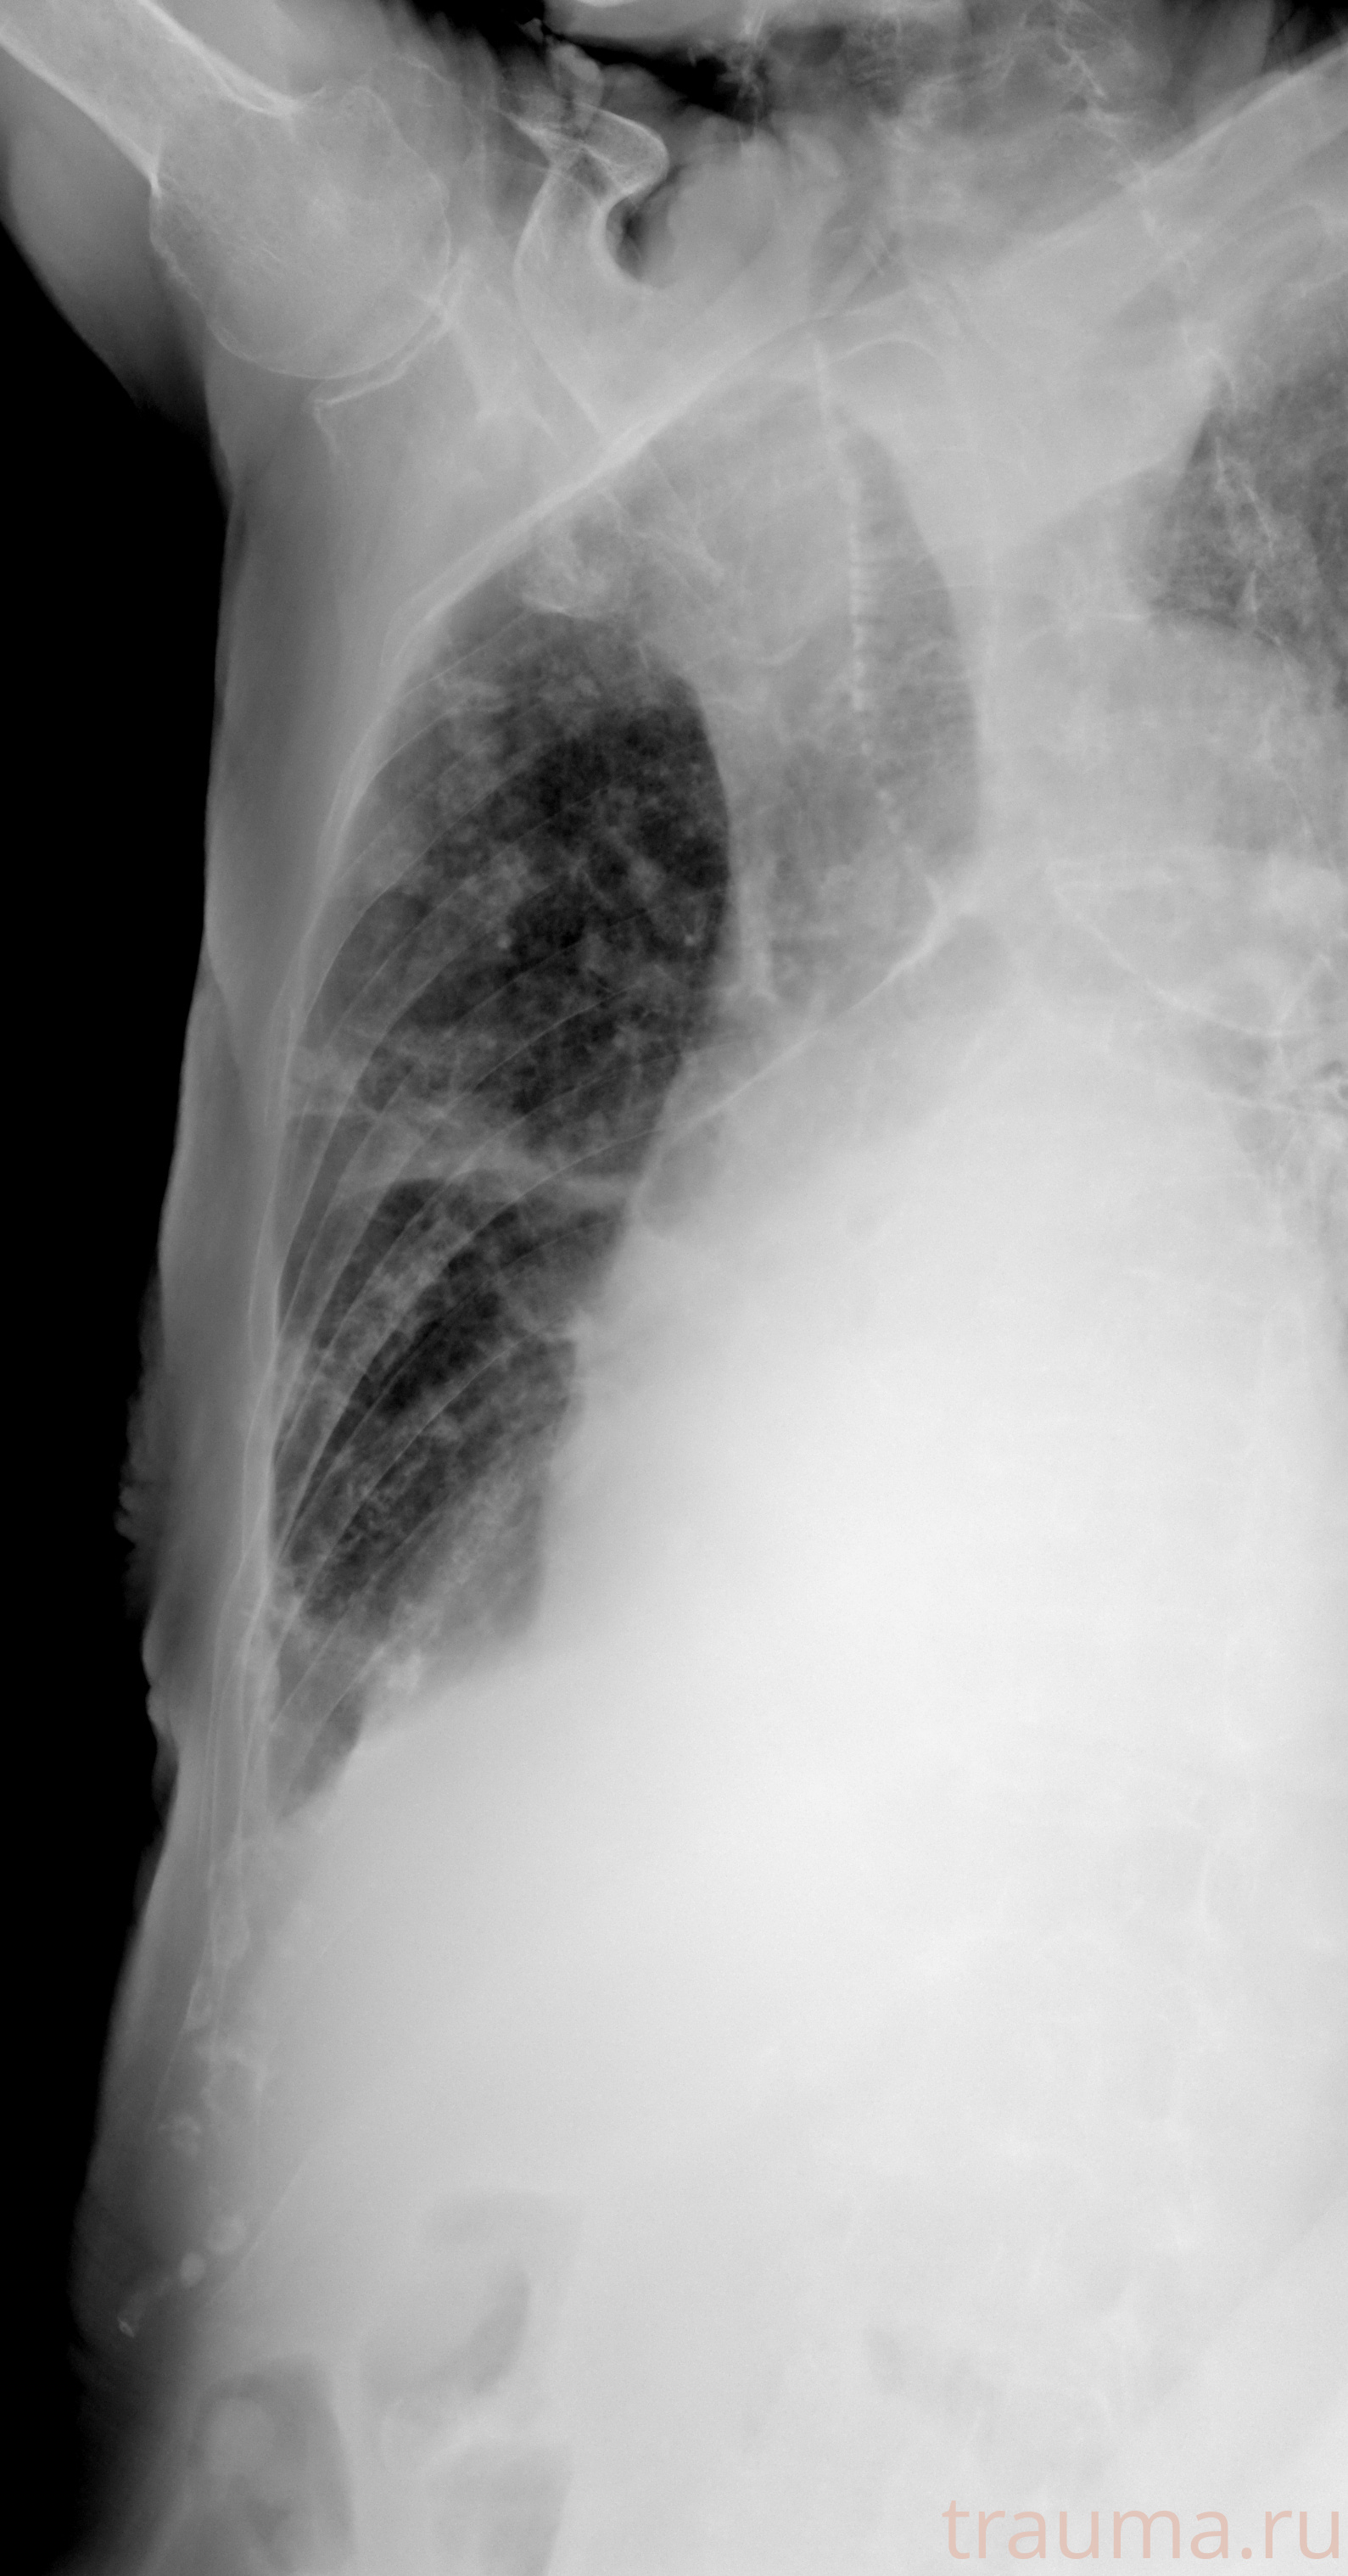

Рентген на дому: по вашему адресу приезжает врач-рентгенолог, травматолог-ортопед с мобильным рентгеновским аппаратом, проводит диагностику травмы или заболевания, делает необходимые рентгенограммы, дает рекомендации по дальнейшему лечению. Получить качественные снимки в домашних условиях возможно благодаря уникальной методике, разработанной МосРентген Центром для института  Склифосовского

при переломе шейки бедра и пневмонии от компании МосРентген Центр - партнера Института имени Склифосовского